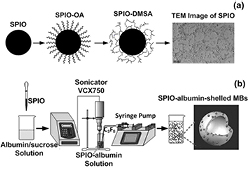

Figure 1 illustrates the procedures in preparing SPIO-albumin-shelled perfluorocarbon MBs (referred to as SPIO-albumin MBs), which includes two major steps: synthesis of SPIOs (figure 1(a)) and assembly of SPIO-albumin MBs (figure 1(b)).

Figure 1. Schematic diagram of multifunctional agent preparation. (a) Monodisperse hydrophobic Fe3O4-OA nanoparticles are firstly synthesized from Fe source. Then, water-soluble SPIOs are obtained via surface double-exchange with DMSA. The transmission electron microscopy (TEM) image illustrates the water-soluble SPIOs remain a monodisperse status with a diameter range between 8–12 nm. (b) Based on a sonicating method, SPIOs are loaded to albumin-shelled perfluorocarbon MBs to fabricate multifunctional imaging and therapeutic agent.

Standard image High-resolution imageFirstly, aqueous solution of FeCl3•6H2O and FeSO4•7H2O was made to serve as a source of iron. Under nitrogen atmosphere to prevent oxidation, concentrated NH3•H2O was added into the iron-containing solution until its pH reached 11.0. Then, oleic acid (OA; Sinopharm Chemical Reagent Co, Ltd, Shanghai, China) was added into the alkaline solution to get mono-disperse hydrophobic Fe3O4-OA nanoparticles. Via a surface double-exchange reaction between OA and meso-2, 3-Dimercaptosuccinic acid (DMSA; Sinopharm Chemical Reagent Co, Ltd, Shanghai, China), mono-disperse water-soluble SPIO (Fe3O4-DMSA) nanoparticles could be obtained and collected through a magnetic separation procedure. After a pH neutralization process, the SPIO solution was dialyzed through the dialysis membranes (Cellu-Sep T3, Membrane Filtration Products Inc, Seguin, Texas, USA) in pure water environment for 3 d to remove excess impurities. The final sample was filtrated through a 0.22 μm membrane and stored at 4 °C. In the second step, SPIO-albumin MBs were synthesized by using a sonicating method similar to that reported by Porter et al (1995). Briefly, 10% bovine serum albumin and 60% sucrose were mixed with a volume ratio of 1:1 in deionized water. A certain amount of SPIOs were then added into the mixed solution. The mixed solution was put in a bell-like glass chamber (9 cm radius and 20 cm height) saturated with perfluorocarbon (C3F8) overnight, then sonicated with an ultrasonic processor (VCX750, Sonics and Materials Inc, Newtown, CT, USA) for 2 min, while a syringe pump (LEGATO 270, KD Scientific Inc Holliston, MA, USA) was used to continuously inflate C3F8 gas. The ultrasonic processor worked at the burst mode with an on/off ratio of 3:1, a working frequency of 20 kHz and an intensity of 300 W. Then, SPIO-albumin MBs were centrifuged and then washed to eliminate free SPIOs. Finally, the upper layer of MB suspensions was collected for subsequent assessments. The detailed description of synthesis procedures can be found in the supplementary data (stacks.iop.org/PMB/59/226729/mmedia).